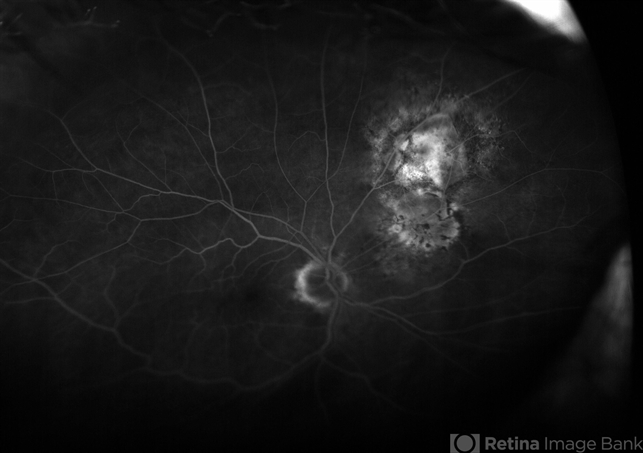

- choroidal nevus

- Tom Steele CRA Midwest Eye Institute Indianapolis, In

Fundus camera

Optos